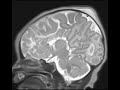

Corpus Callosum Agenesis

These images obtained as an ultrafast protocol for a newborn infant show the characteristic features of agenesis of the corpus callosum (CC). The lateral ventricles are parallel and on coronal imaging are reminiscent of bull horns. The occipital horns are dilated and have a colpocephalic appearance. The third ventricle is elevated and contiguous with the interhemispheric fissure. On sagittal imaging, the cingulate gyrus is absent. Incidentally noted is caput succedaneum. Agenesis of the CC brain is commonly sporadic and can be seen with other brain malformations such as Dandy Walker.